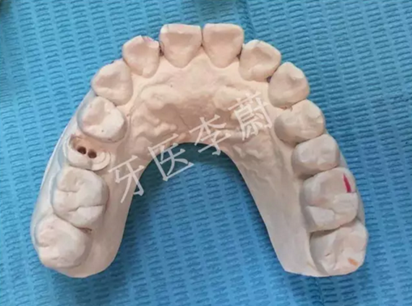

15牙模型

15牙二氧化鋯烤瓷冠舌面觀